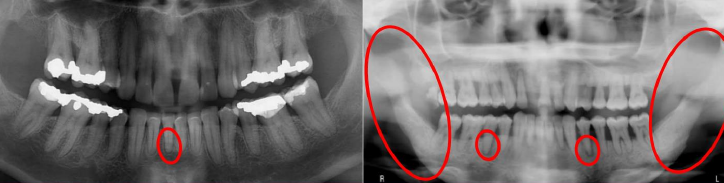

Papillon-Lefèvre Syndrome GENE: cathepsin C gene 手掌與腳底

• Cathepsin C: 溶酶體內蛋白酶

• 手掌與腳底的角質化

• 皮膚病灶的治療:維 A 酸類(systemic retinoids)

• PMN 功能不足 → 嚴重牙周病

• 快速的骨流失 → floating in air

• 瀰漫出血與增生性牙齦炎

Tuberous Sclerosis

(結節型硬化症, Epilolianuria)

體顯性,

GENE: TSC1, TSC2

-

• 緻密的纖維結締組織增生

• 下顎 radiolucent lesion

• 血管纖維瘤(angiofibroma): 鼻翼, 指甲旁